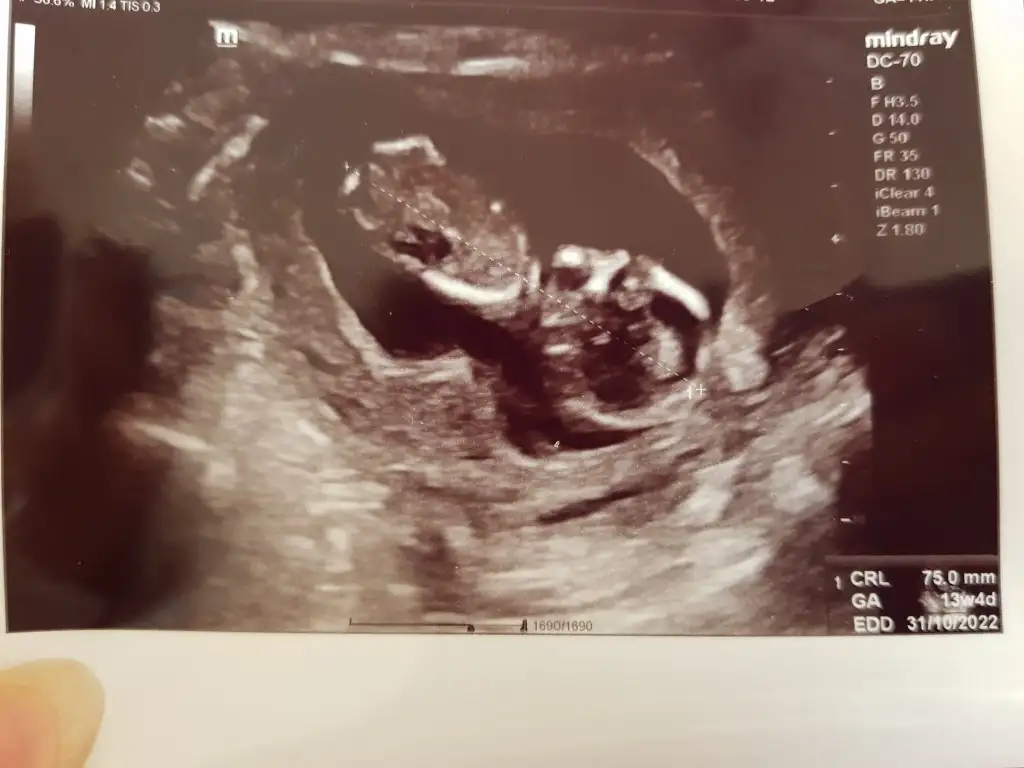

Ilk foto 13+4